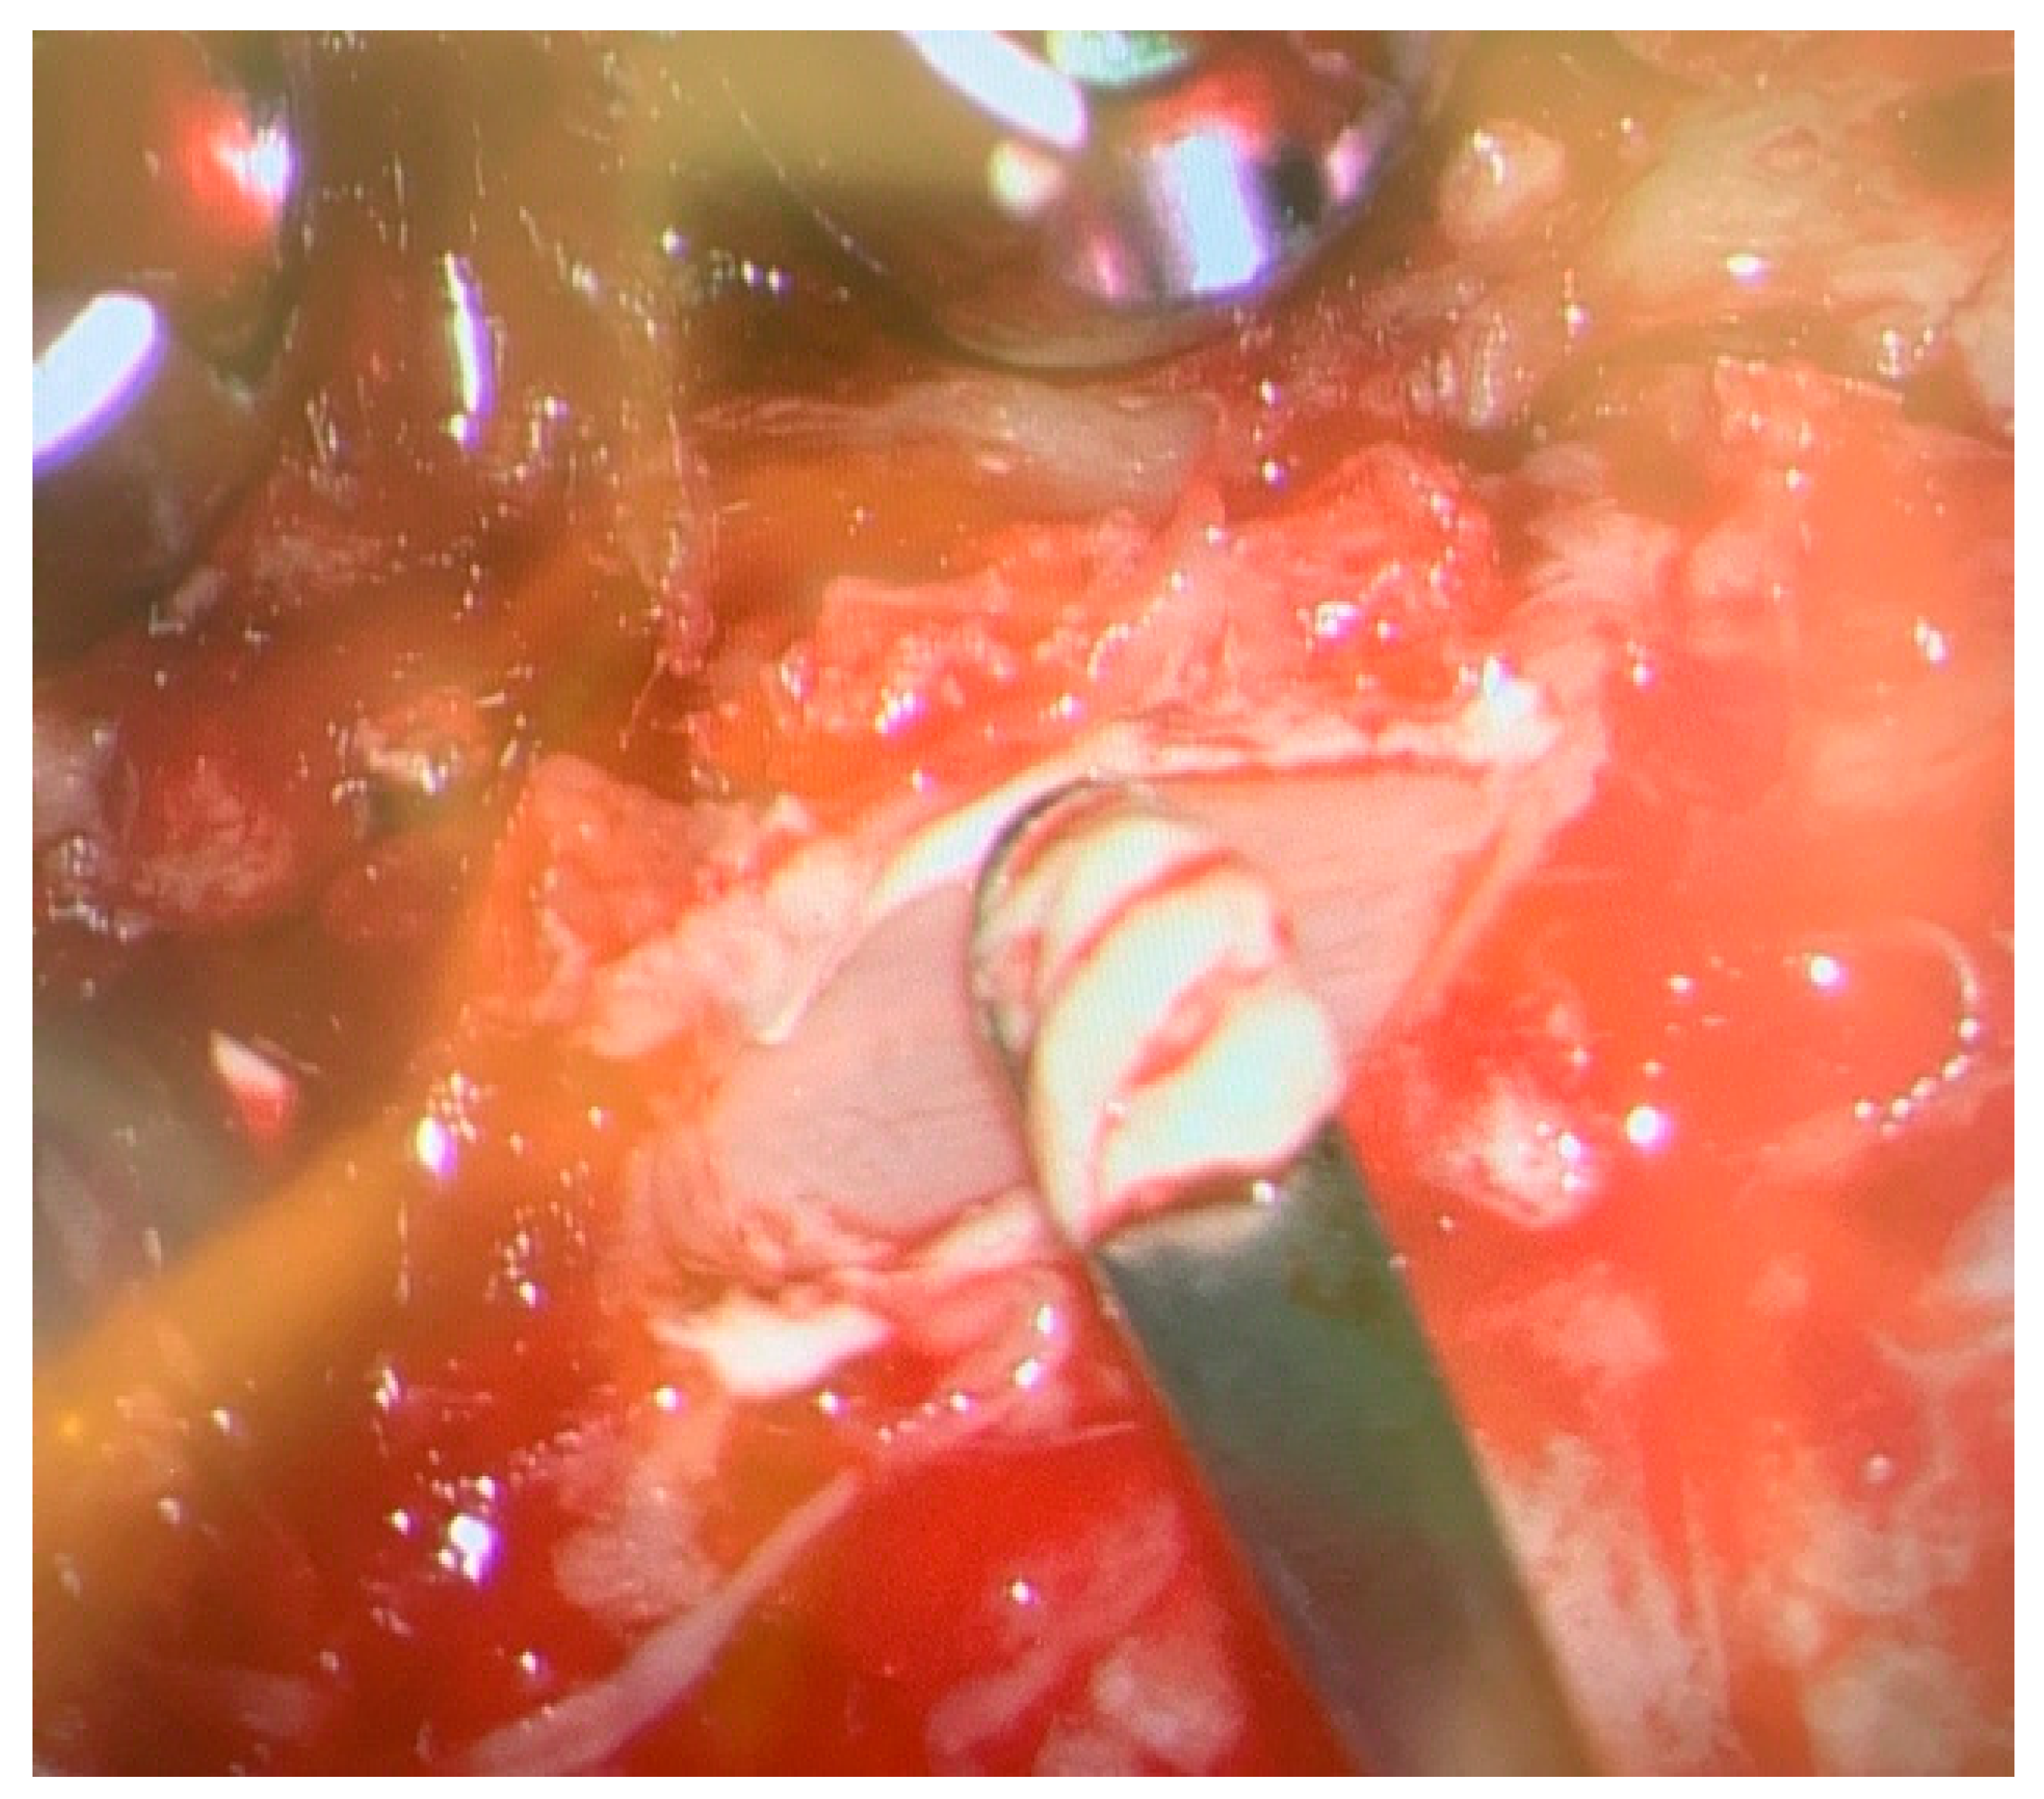

During the procedure, chalky white deposits were observed in the right-sided epidural space at the level of C4, overlying the ligamentum flavum. These deposits were removed in a piecemeal fashion, decompressing the spinal cord. Specimens were collected and sent for histopathological examination and culture. Baseline neuromonitoring showed weak somatosensory evoked potentials (SSEP) and motor evoked potentials (MEP) in both the upper and lower limbs, with no signs of nerve irritation detected on electromyography (EMG).

Figure 3. Intraoperative image showing chalky white deposit over the ligamentum flavum at.cervical 4 level.

Spinal Gout cases are treated either conservatively or surgically based on presence or absence of neurological deficit. Pharmacological treatment is reserved for less severe cases without having signs and symptoms of radiculopathy and myelopathy. Medications such as NSAIDS, Colchicine and corticosteroids are used mainly used for symptoms relief in acute attacks without effecting deposition of tophi in tissues and boney erosions. If the patient has a history of hypertension, heart disease, chronic kidney disease, gastric or duodenal ulcers, NSAIDS allergy and receiving anticoagulant therapy then colchicine should be used in spite of NSAIDS. Anti gout medications which are divided into first- and second-lines medications are used to prevent further gout attacks with a goal to keep uric acid level less than 6 mg/dl. First line anti Gout medications mainly reduce uric acid production which include Xanthine oxidase inhibitors include allopurinol, oxypurinol and febuxostat and second line medications are Uricosuric agents which increase uric acid excretion having sulfinpyrazone and probenecid in the list. Surgical treatment is indicated when there is spinal cord or nerve roots compression with neurological deficit. The main goal of the surgery is to decompress the spinal cord and nerves with removal of tophi which looks like chalky white material [17]. We did decompression of the cervical spine in our first case with removal of chalky white material during the surgery because radiological images were showing compression of cervical spinal cord with progressive neurological deficit and the 2nd case was managed conservatively because the patient gave a good response to anti gout medications with improvement in clinical symptoms, declining uric acid level and complete resolution of thoracic spine facet cyst on follow up MRI spine.